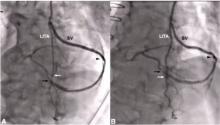

Can a Single ITA Composite Graft Adequately Supply the Heart? [1]

Marc Ruel of the University of Ottawa Heart Institute, Ottawa, Canada, poses the question: can a single ITA composite graft adequately supply the heart? Dr. Ruel references numerous studies and draws on his own clinical experience in this talk.